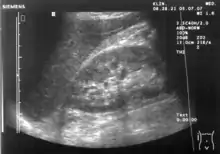

تخطيط الصدى البطني أو تصوير البطن بالموجات فوق الصوتية (بالإنجليزية: Abdominal ultrasonography) (يُسمى أيضًا التصوير فوق الصوتي في البطن) هو شكل من الأشكال الطبية للتصوير بالموجات فوق الصوتية (التطبيق الطبي لتقنية الموجات فوق الصوتية) لرؤية أعضاء البطن التشريحية. يعتمد هذا الجهاز علي إرسال واستقبال الموجات فوق الصوتية لتصوير الأعضاء الداخلية من خلال جدار البطن (بمساعدة الهلام الذي يساعد على انتقال الموجات الصوتية). لهذا السبب يُطلق على هذا الإجراء اسم الموجات فوق الصوتية عبر البطن، عكس الموجات فوق الصوتية بالمنظار الذي يجمع بين الموجات فوق الصوتية مع المنظار لرؤية الأجزاء الداخلية من داخل الأعضاء المجوفة.

يمكن استخدام الموجات فوق الصوتية في البطن لتشخيص التشوهات التي تصيب الأعضاء الداخلية المختلفة، مثل الكلى[1] والكبد والمرارة والبنكرياس والطحال والشريان الأبهر البطني. إذا تمت إضافة التصوير بالدوبلر، يمكن كذلك تقييم تدفق الدم داخل الأوعية الدموية (على سبيل المثال: للبحث عن تضيق الشريان الكلوي). يستخدم عادة لفحص الرحم والجنين أثناء الحمل. وهذا ما يسمى التصوير بالموجات فوق الصوتية التوليدية.[2][3]